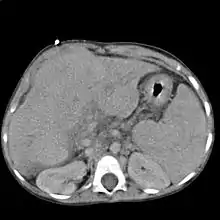

تستخدم أشعة الموجات فوق الصوتية بشكل روتيني في تقييم مدى تشمع الكبد، حيث إنها قد تظهر الكبد المتشمع في مراحله المتقدمة في شكل كبد صغير وعقيدي الشكل، بالإضافة إلى زيادة ارتجاع الصدى في الأشعة وظهور أجزاء غير منتظمة الشكل. كذلك من الممكن أن تُظهر أشعة الموجات فوق الصوتية وجود سرطان بخلايا الكبد وارتفاع ضغط الدم في الوريد البابي ومتلازمة بود-كياري (من خلال تقييم معدل تدفق الدم في الوريد الكبدي).

تتضمن الاختبارات الأخرى التي يتم إجراؤها في ظروف معينة التصوير بالأشعة المقطعية CT للبطن والتصوير بالرنين المغناطيسي MRI للكبد والقنوات المرارية (تصوير البنكرياس والقنوات المرارية بالرنين المغناطيسي MRCP).